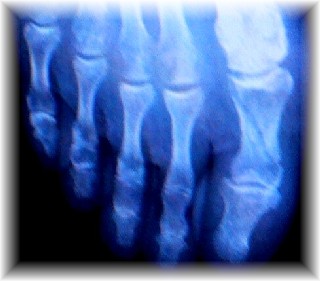

斜めに折れています。

他に小指の根元の方も2ヶ所折れています(レントゲン写真では見えにくい)

右1趾基節骨骨折・右足根骨多発骨折 が傷病名です。

前者(斜めに折れている部分)はピンで固定する手術が必要、

後者は放っておいていいとのこと。(ただし、動かないように固定)